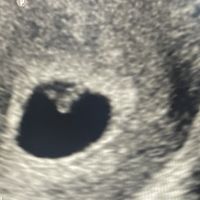

Adjunto ecografía abdominal de 13+4. A mí me a la sensación de niña, pero no estoy segura.jeje